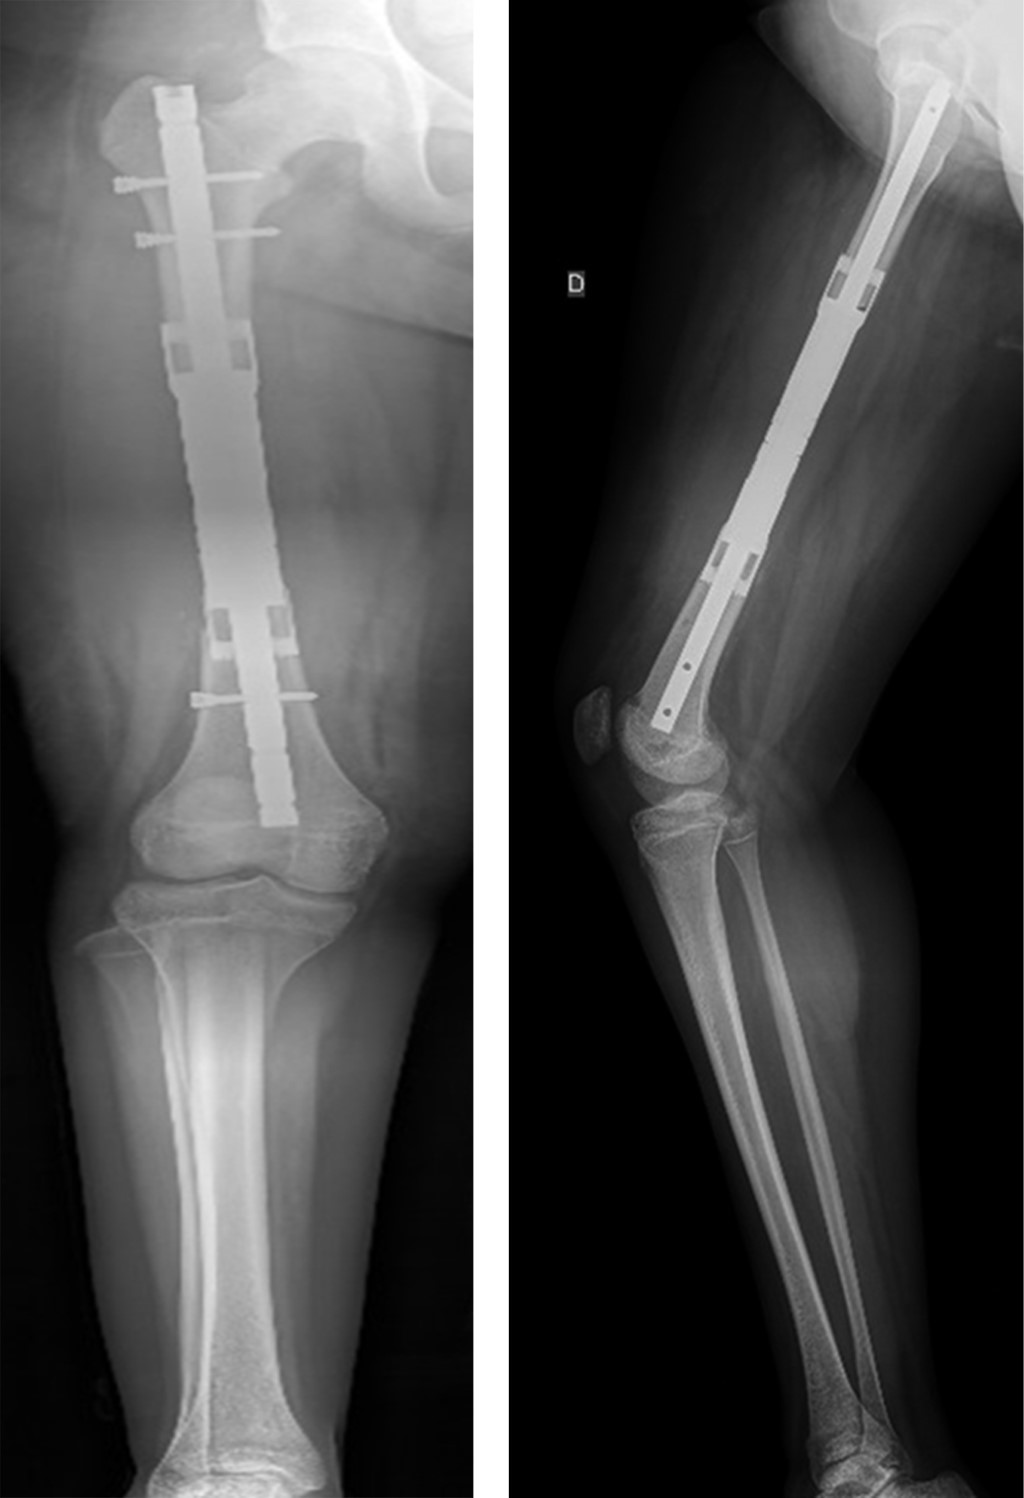

Con la paciente bajo anestesia general y en decúbito supino, se realiza asepsia, antisepsia y colocación de campos quirúrgicos estériles. Se opta por un abordaje anteromedial de fémur, mediante incisión longitudinal de aproximadamente 25 cm, disecando por planos hasta encontrar intervalo entre músculos recto femoral y vasto medial; después se encuentra el vasto intermedio, el cual se diseca hasta encontrar diáfisis femoral. Se observa tumoración en tercio medio de diáfisis femoral de aproximadamente 13 cm de longitud por 3 cm de ancho, el cual se reseca con bordes amplios, realizando osteotomía a 16 cm proximales de superficie articular de la rodilla (Figura 3); se envía muestra medular transquirúrgica, recibiendo confirmación de presencia de bordes libres por el Servicio de Patología. Se realiza segunda osteotomía a 16 cm distales del trocánter mayor, se envía segunda muestra de médula ósea, recibiendo reporte negativo para células malignas. Se realiza rimado de fémur proximal y distal con rimas diámetros 9, 10 y 10.5 hasta atravesar fosa digital proximalmente; se coloca asentador para hueso, regularizando el límite de la osteotomía. Se introduce clavo endomedular hasta limite distal establecido (Figuras 4 y 5) y se coloca prótesis diafisaria (Figura 6) con asentadores y coronas en extremos diafisarios, respectivamente. Se procede a colocar pernos de bloqueo, verificándose longitud de extremidad (Figura 7) comparando con la contralateral. Se repara intervalo entre recto femoral y vasto medial y se procede a cierre por planos.

Figura 7